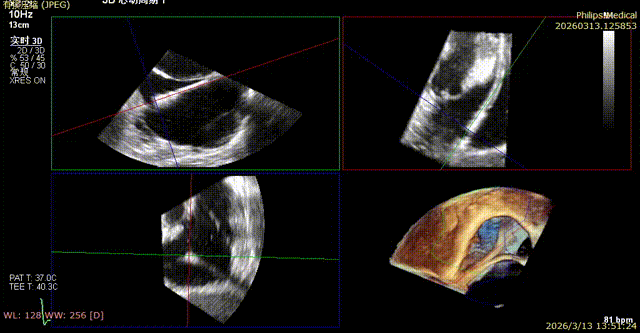

Postoperative regurgitation baseline

Postoperative tricuspid annular area: 7.68 cm²

Following annuloplasty, leaflet coaptation was improved compared with the preoperative state, and regurgitation was reduced from severe to trivial.

1. The tricuspid annulus was significantly reduced, and the degree of regurgitation was reduced from severe to trivial, with a marked improvement in regurgitation. Although the coronary artery course was somewhat affected intraoperatively, blood supply remained normal. For patients at high coronary risk with concomitant tricuspid regurgitation, the outcome exceeded expectations and successfully alleviated the patient’s burden.